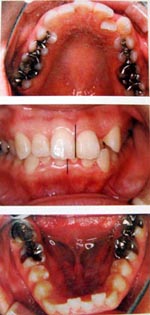

成人の場合・1日10時間装着

顎が小さく症状がある方には有効です。